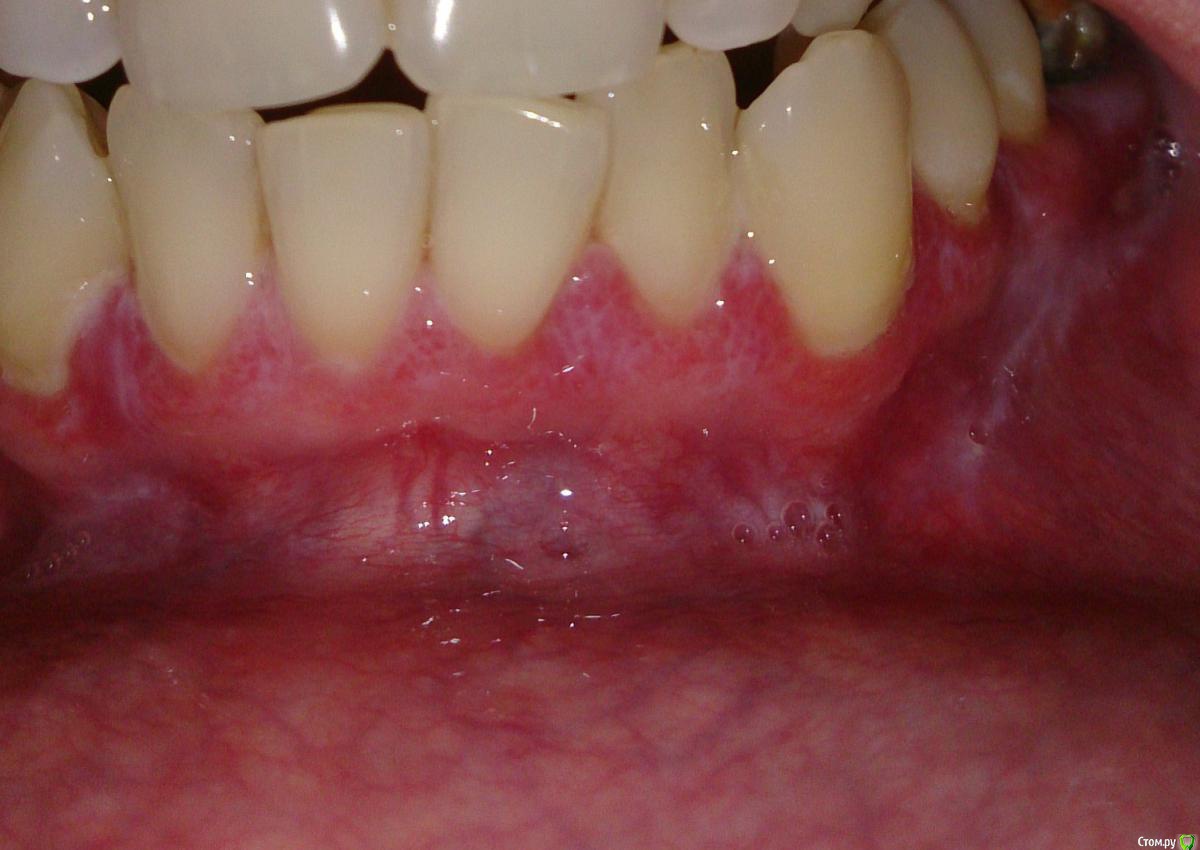

Милanora Опубликовано 4 января, 2017 Поделиться Опубликовано 4 января, 2017 Добрый день! Помогите пожалуйста, не знаю что уже и думать. Проходила лечение у стоматолога и парадонтолога, врачи в один голос говорят, что у меня классический КПЛ и если меня он не беспокоит, то лечить его и не нужно. Десны иногда побаливают, но язвочек нет. Решила еще для очистки совести сходить к дерматологу. Сделала мазки на грибок, отрицательно. Врач дерматолог сказала, что лечением слизистой стоматологи занимаются, но согласилась посмотреть. КПЛ отменила, сказала, что если он есть на слизистой рта, то и на теле обязательно должен быть. У меня нет никаких высыпаний на теле. Поставила лейкоплакию, на мой вопрос, от чего она вообще бывает (я курю и у меня неправильный прикус, отчего иногда прикусываю щеку) она послала сдавать анализ на ВИЧ, а курение и прикус не могут быть причиной, по ее словам. Я вообще в шоке.Посмотрите пожалуйста фото, может быть Вы что-то подскажите мне.... Ссылка на комментарий

Л Ю С Я Опубликовано 4 января, 2017 Поделиться Опубликовано 4 января, 2017 По фото у Вас одна из разновидностей КПЛ. Может быть изолировано поражение слизистой. Для окончательного диагноза нужен очный осмотр стоматолога. Курение обязательно нужно исключить Ссылка на комментарий

Salma Опубликовано 5 января, 2017 Поделиться Опубликовано 5 января, 2017 тоже склоняюсь к кпл Ссылка на комментарий

ПалСаныч Опубликовано 5 января, 2017 Поделиться Опубликовано 5 января, 2017 Имхо кпл Ссылка на комментарий